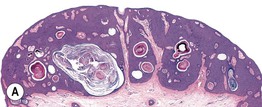

• Histopathology: a spectrum of different architectures, most commonly acanthotic, papillomatous and hyperkeratotic, or irritated (Fig. 89.2).

Fig. 89.2 Seborrheic keratoses – spectrum of histologic subtypes. A Acanthotic type with lobular hyperplasia with prominent horn cysts. B Papillomatous or hyperkeratotic type with church spires of papillomatosis and hyperkeratosis. C Irritated seborrheic keratosis. Exophytic lesion with papillomatosis, hyperkeratosis, hemorrhagic crust, and dermal inflammation. A, B, Courtesy, Luis Requena, MD; C, Courtesy, Lorenzo Cerroni, MD.